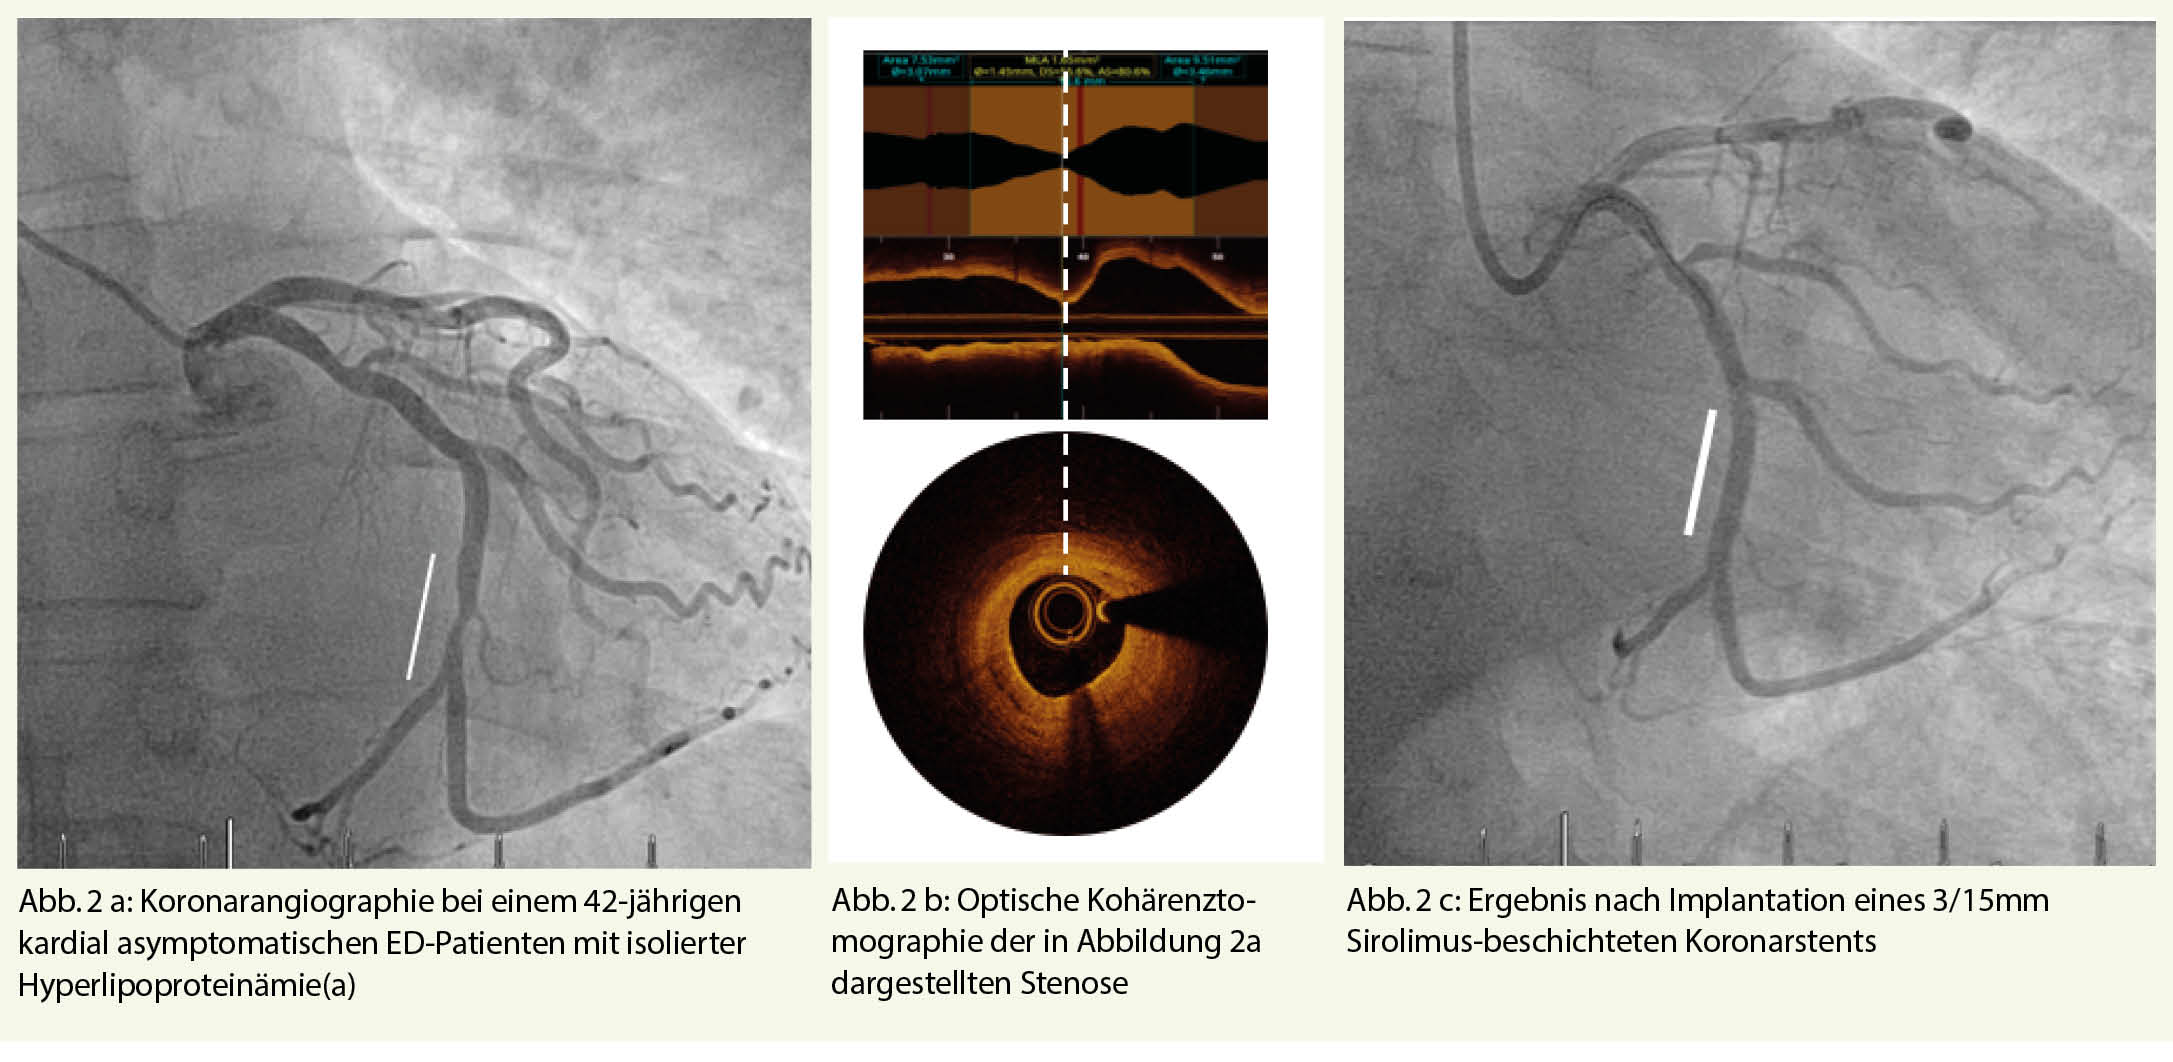

Sobald die Diagnose einer arteriell bedingten ED gesichert ist, empfiehlt sich ein fachärztliches Workup. Häufig finden sich bei Patienten mit arteriell bedingter ED auch Pathologien in anderen arteriellen Stromgebieten (Abb. 1, 2).

Eine von uns kürzlich publizierte Studie zeigte, dass die meisten Befunde, die eine sofortige Behandlung erforderten, im Zusammenhang mit koronar-arteriellen Verkalkungen standen. Solche wurden bei Kontrastmittel-verstärkter CT-Untersuchung bei 37,5% der ED-Patienten beobachtet.

Insgesamt zeigten in dieser Arbeit 168/200 (84,0%) männliche Patienten mehrere zufällige CT-Befunde. Andere häufige Zufallsbefunde sind Aneurysma, Tumore, Prostata-Hyperplasien, Steatosis hepatis, Kolon-Divertikulose, Hernien, Nieren- und Leberzysten und Degeneration des Spinalkanals (5).